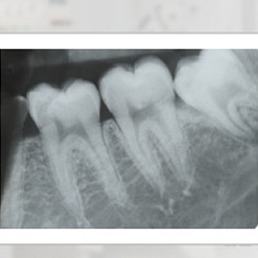

X-ray examination covering the area of 1-3 teeth. It shows crowns, root apices and tissues around the examined teeth.

- Periapical X-ray – allows for detailed imaging of a single tooth or its section. Most often used for root canal treatment or suspected cavities in hard-to-reach areas.